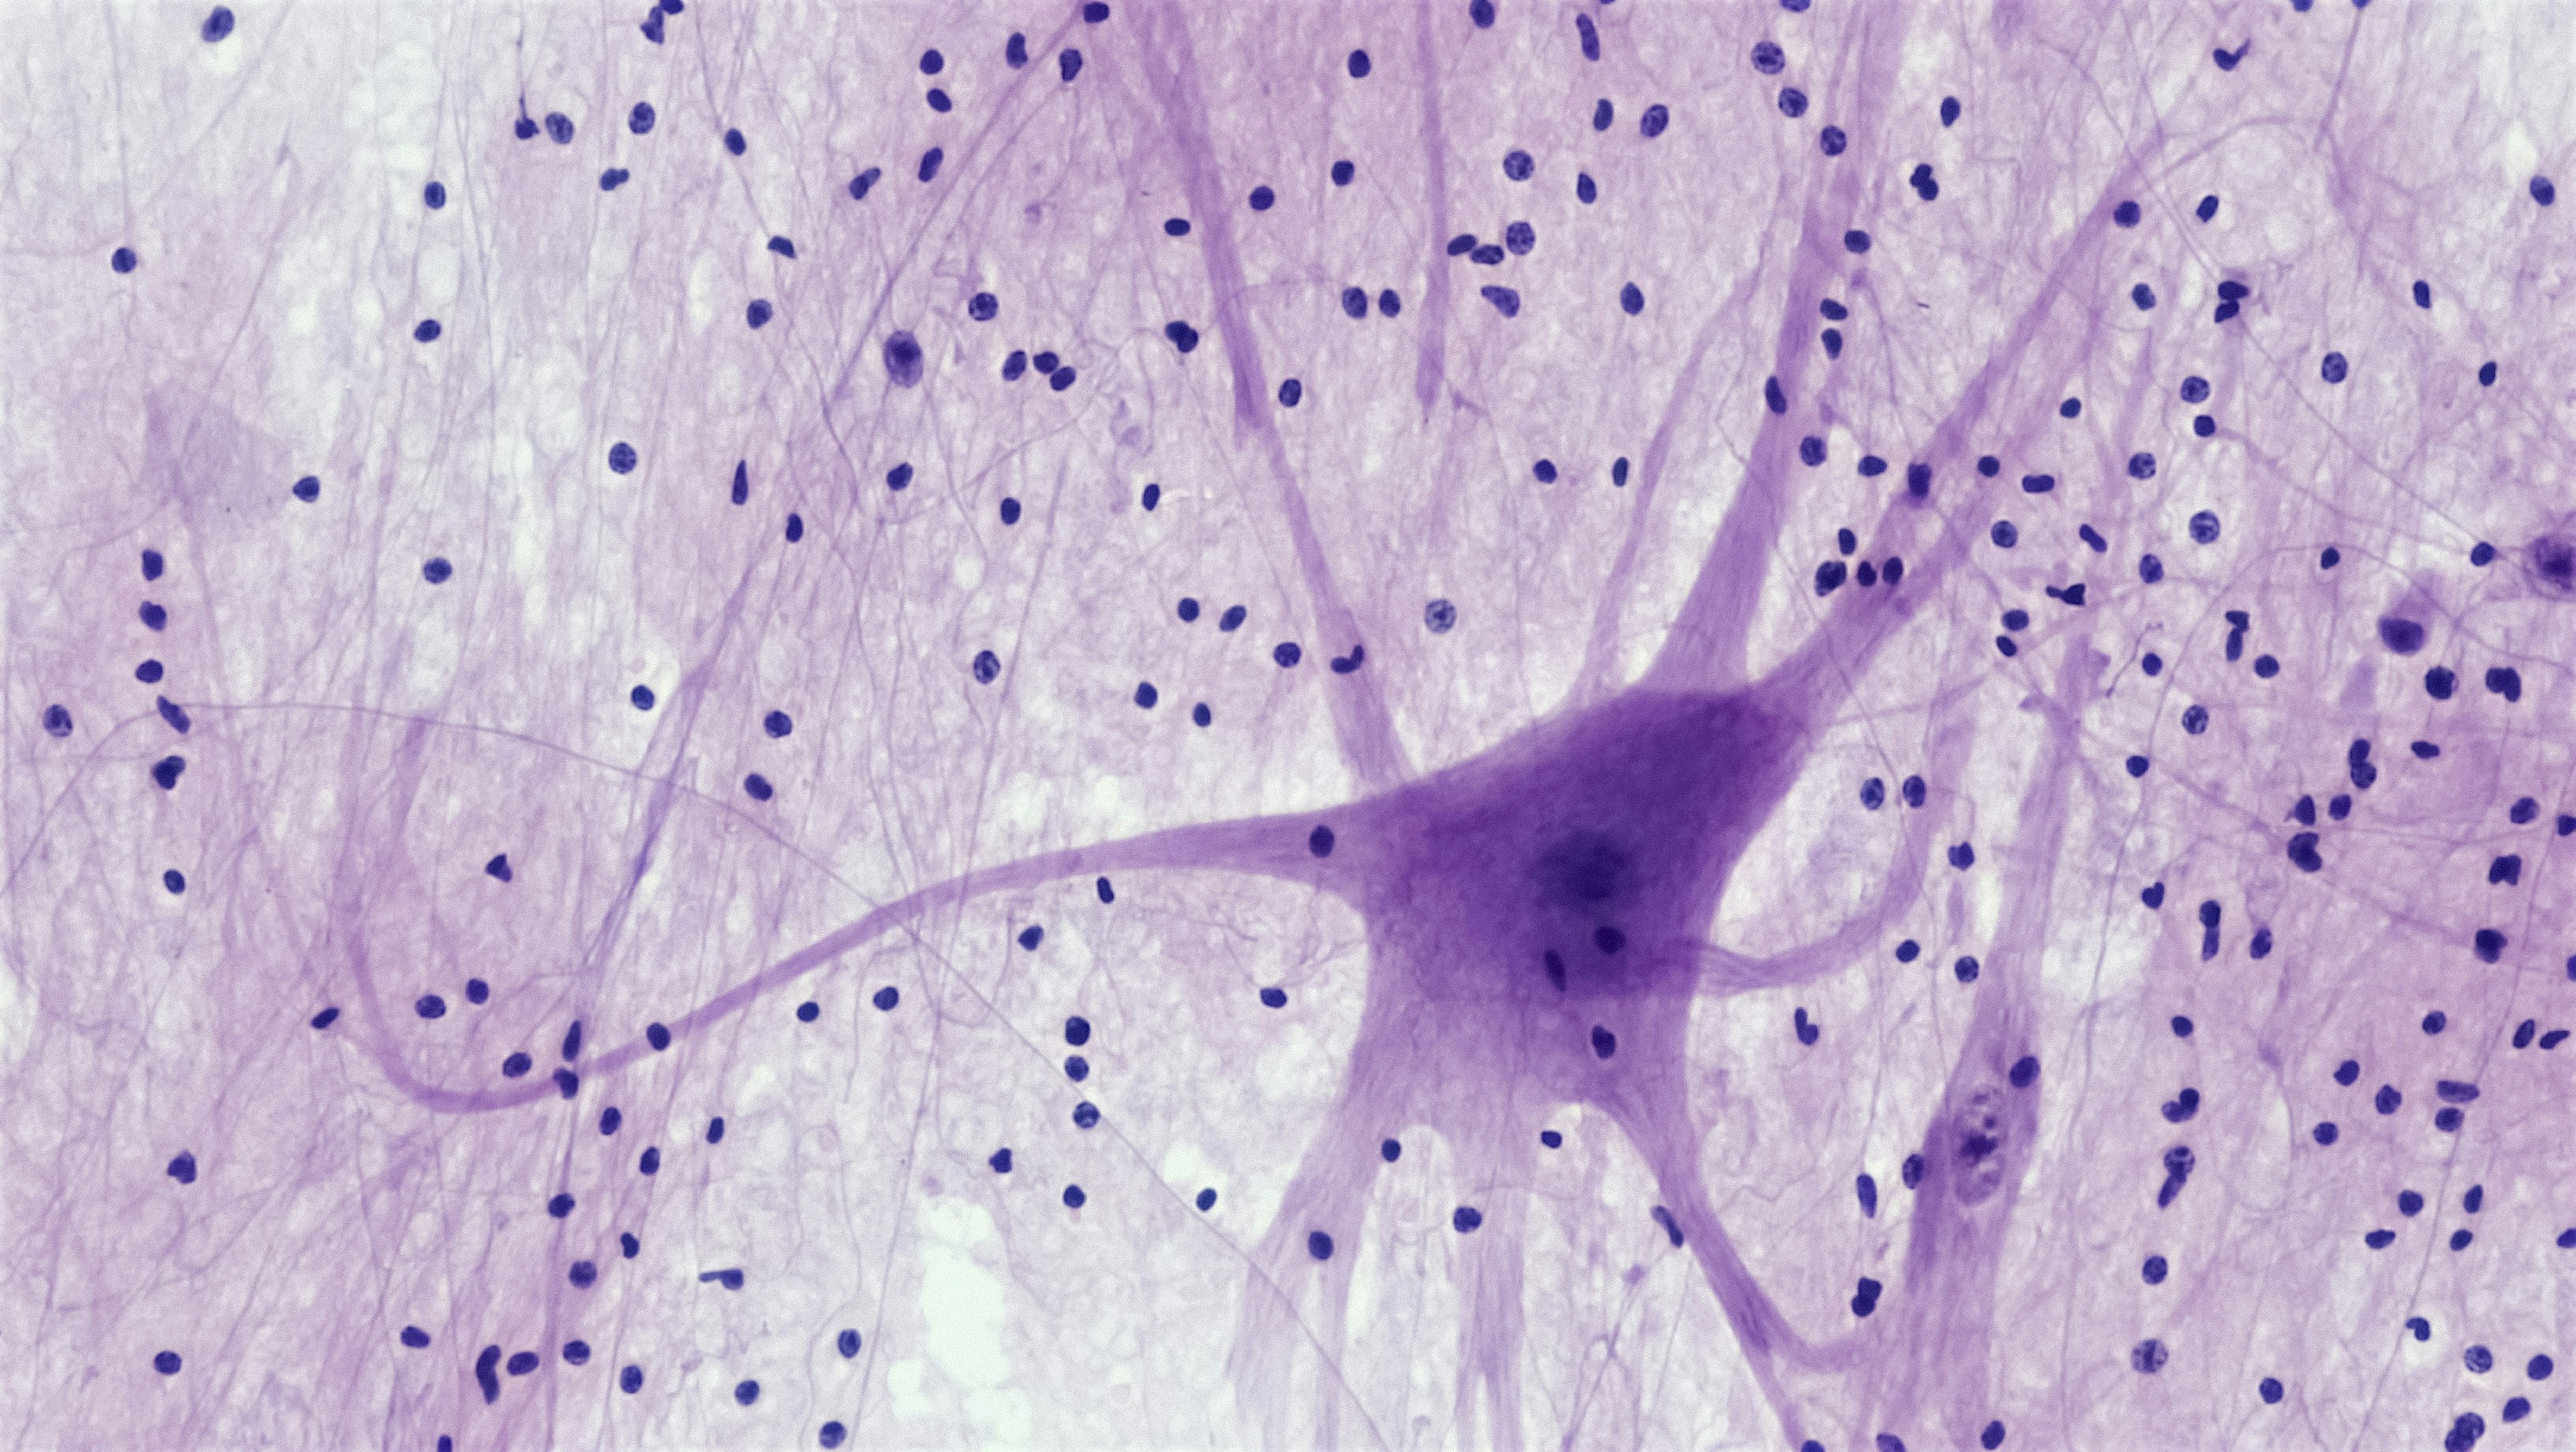

Descubre todo sobre la investigación profunda de la mente, un análisis detallado que te llevará a explorar los rincones más intrincados de tu cerebro.